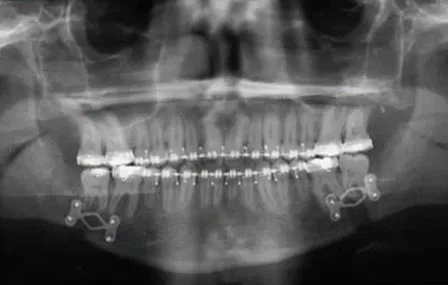

Après les repositionnements condyliens et les synthèses par plaques vissées et lors de la levée de la fixation maxillo-mandibulaire (FMM), on peut rencontrer en particulier dans les avancées corporéales un décalage de l’occlusion, uni-ou bilatéral, qui amène à reprendre la FMM, puis à déposer les vis antérieures et à les reposer en os « sain ».

Le nouveau forage est fréquemment très proche du précédent, ce qui rend instable l’insertion des vis et nécessite la dépose et la repose complète du matériel

Permettre le réglage occlusal fin après la levée de la FMM, sans dépose du matériel d’ostéosynthèse

Deux types de plaques :

Plaques à repositionnement ajustable

Plaques déformables. Plaques "en losange" : deux longueurs

+ /-2 millimètres

Au-delà : dépose de la plaque et nouvelle pose

Eviter les « allers-retours » pour prévenir le phénomène de fatigue du métal